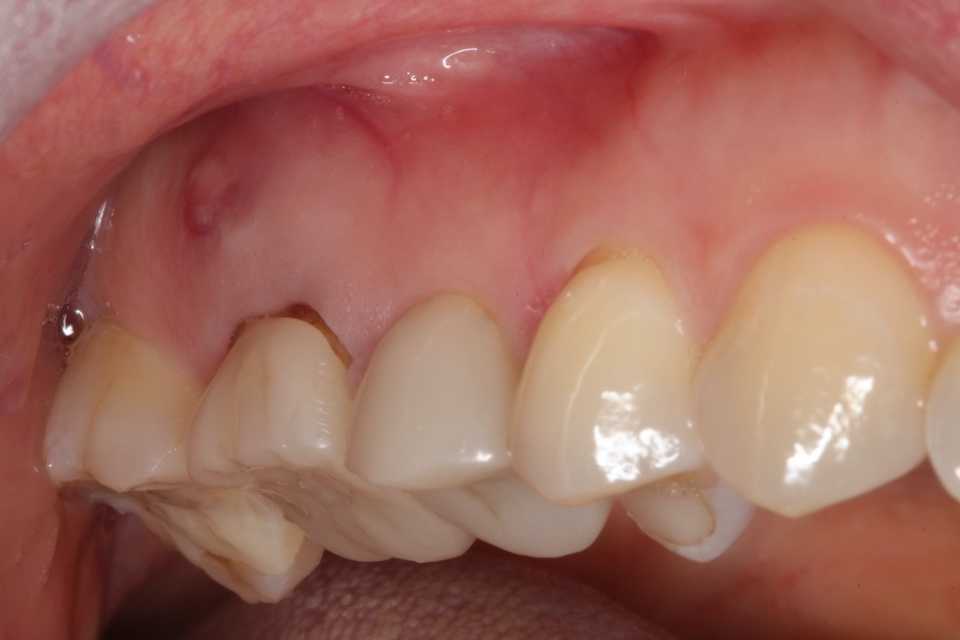

当時40代男性、咬合性外傷(常時食いしばって?嚙み鳴らして?いるのを普通でむしろいいことだと思い込んでいた)臼歯部に多数のクラック、歯冠・歯根破折、2次カリエスが認められた。今日はこの時のつづきで、コロナ騒動を挟んで4年後のお話です。とうとう左上7が壊れたというのと、別記事になるのだけれど右下7が腫れたという件で来院された。https://plaza.rakuten.co.jp/mabo400dc/diary/202602080001/今日の記事はこの時の抜歯・再植を参考にされるとよく分かると思う。https://plaza.rakuten.co.jp/mabo400dc/diary/202602070000/まずレントゲン写真では近心部分が壊れて虫歯になっている。上のリンク記事の術後のレントゲン写真と見比べると問題範囲が分かると思う。口蓋側頬側面観。かなり壊れている。神経(歯髄)が無くなった歯は神経がある歯よりも歯質が脆くなっているので、崩壊が早い。補強連冠がなかったらとっくにバラバラになって崩壊していただろう。神経がなくなると歯は枯れ木状態になるので長持ちしない。特に外傷性咬合があり微小クラックがたくさんあるといわゆる金属疲労現象で崩壊する。なるべく歯髄は保存しないといけない理由だ。これは前回再建した時の破片だが、今回はCR:ダイレクトボンディングで修復することにしたので使わない。虫歯を除去して新鮮歯質を確保する。歯肉縁下だがフィニシングラインを明示する。後はCRで充填していくだけだ。トリミングして今回は部分修復で終わる。これで崩壊が止まるというわけではないが、先送りすることはできる。6